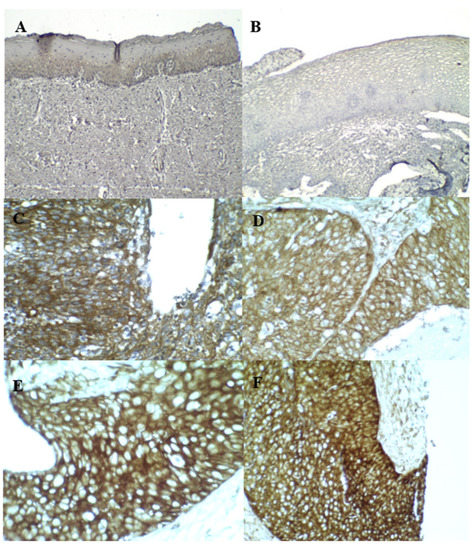

3.3. p16INK4A and Ki–67 Immunostaining

3.4. Cortactin Immunostaining